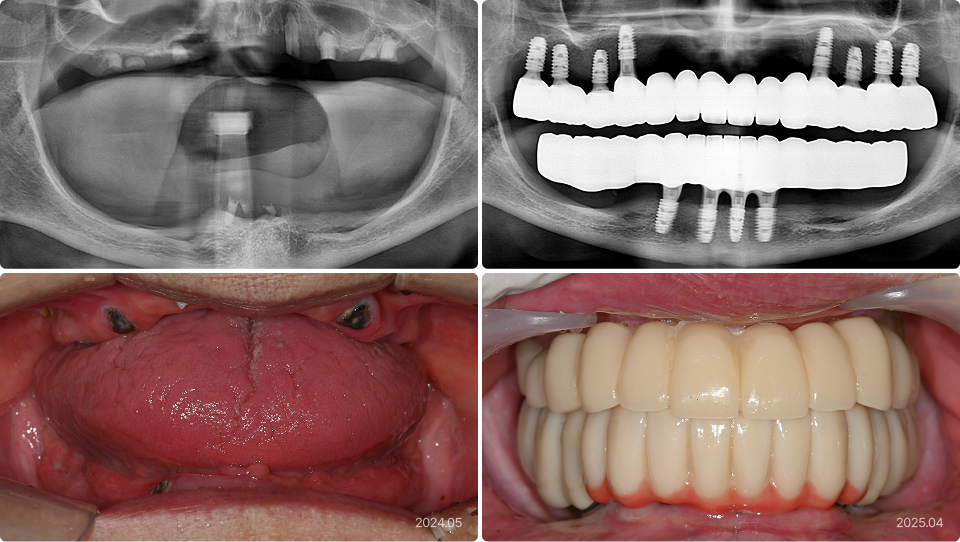

93세, 남

“다른 치과에서 임플란트 틀니 했다가 실패했어요.

틀니는 싫고, 나이가 많은데 임플란트가 가능할까요?”

치료 전

치료 후

• 임플란트 틀니 실패로 인한 걱정

• 고정성 보철을 원하지만 고령으로 전신적, 수술적 부담

• 기존 임플란트 제거 및 단 4개 임플란트 식립으로 부담 최소화

• 전체 12개 치아를 연결하는 고정성 보철로 기능 및 심미 회복